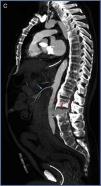

Varón de 56 años con espondilitis anquilosante y anticoagulado, que ingresa tras ser atropellado por un vehículo. A su llegada, en situación de shock hipovolémico, requiere transfusión masiva y administración de fármacos vasoactivos. Eco-FAST negativo. En el TAC se objetiva rotura aórtica, secundaria a lesión espinal por mecanismo de flexión-distracción. En las figuras 1 y 2 se observan cortes axiales con contraste intravenoso (CIV) en fase arterial (A), fase portal (B) y sagital en fase arterial (C), a nivel de L2-L3. La aorta abdominal presenta abundante material hiperdenso adyacente correspondiente a CIV extravasado (flechas) en retroperitoneo, espacio intersomático y al espacio epidural. El paciente es sometido a cirugía urgente, falleciendo periprocedimiento (figs. 1 y 2).